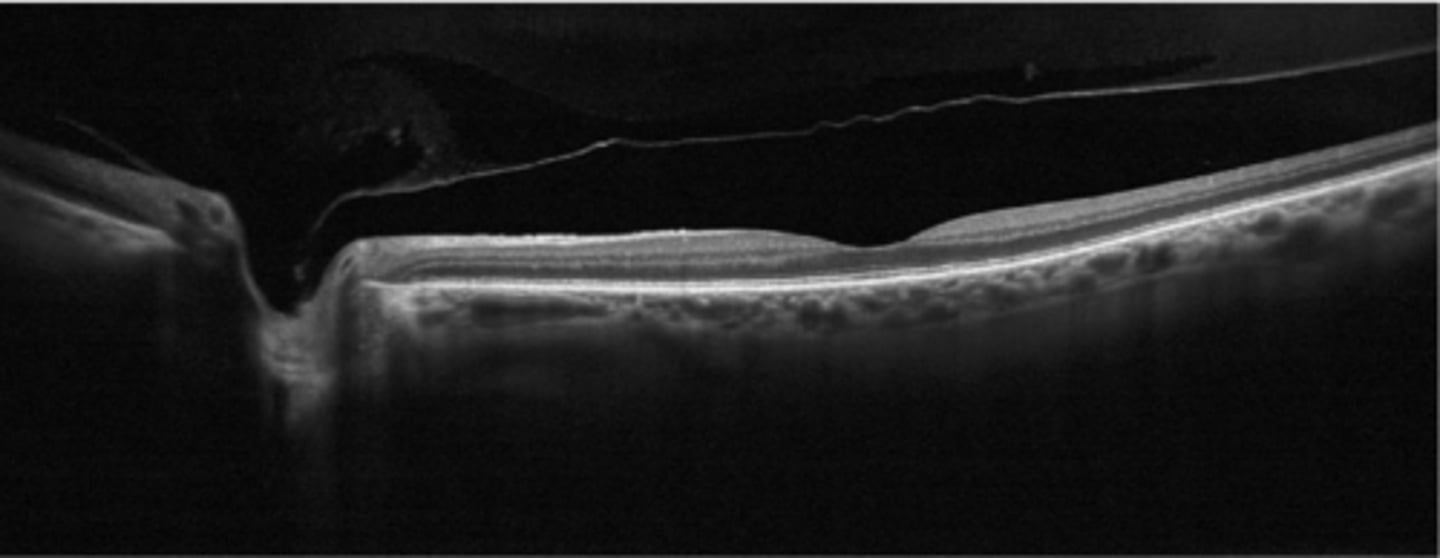

What condition is shown here?

hyaloid membrane separates from retina at the area posterior to the vitreous base

What is a PVD?